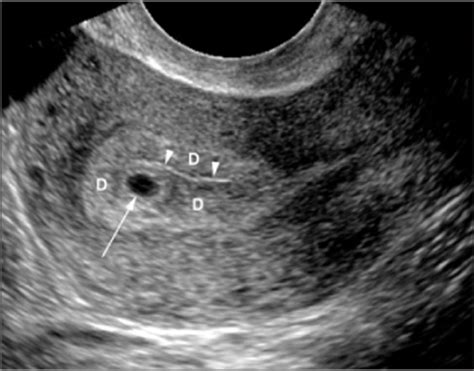

Double Sac Sign

Double Sac Sign. Interobserver reliability and frequency of occurrence the sonographic appearance of early gestational sacs, before visualization of a yolk sac or embryo, is highly variable. Image b is a color overlay of the structures that contribute to the appearance, including the gs, surrounded by the decidua capsularis (light pink), partially surrounded by the decidua parietalis (dark pink).

Gestational sac should be ~6 mm in diameter; This morphologic appearance differs from and excludes the presence of an ectopic pregnancy. Web intradecidual sac sign (idss) is a useful feature in identifying an early intrauterine pregnancy (iup) as early as 25 days of gestation 1. Image b is a color overlay of the structures that contribute to the appearance, including the gs, surrounded by the decidua capsularis (light pink), partially surrounded by the decidua parietalis (dark pink). Web the double decidual sac sign (ddss) is a useful feature on early pregnancy ultrasound to confirm an early intrauterine pregnancy (iup) when the yolk sac or embryo is still not visualized. 20 pdf tools share get access to the full version of this article. Web early iup with double decidual sac sign transvaginal ultrasound shows an early intrauterine pregnancy with double decidual sac sign. Gestational sac should be visible by this time; Is it reliable for diagnosis of early intrauterine pregnancy? Web the first, the double decidual sac sign, was described in 1982 by bradley et al.

Web these two signs are: Web doubilet pm, benson cb. The intradecidual sign is seen before 5 weeks age as a small anechoic area (sac) on either side of the central endometrial echo (uterine cavity line) within the thickened decidua. 1) intradecidual sign and 2) double decidual sign. Gestational sac should be visible by this time; Chiang g, levine d, swire m, et al. Web early iup with double decidual sac sign transvaginal ultrasound shows an early intrauterine pregnancy with double decidual sac sign. [ 3] as two concentric echogenic rings of tissue surrounding the intrauterine sac that protrude into the uterine cavity. The threshold level (earliest one can see the sign) is 24 days of gestation and the discriminatory level (one should always see the sac) is 47 days. Web these two signs are: Web double sac sign and intradecidual sign in early pregnancy interobserver reliability and frequency of occurrence peter m.